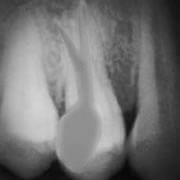

Root Canal Treatment